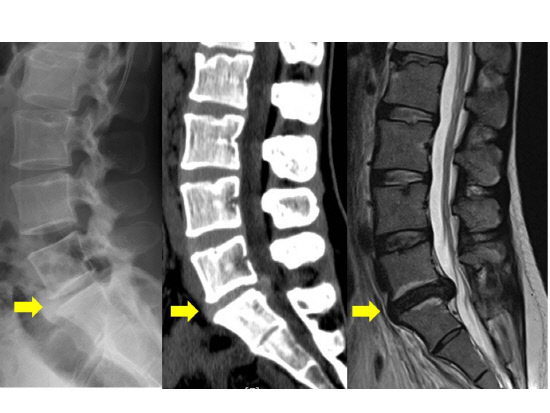

허리디스크에 대해 아직 살펴보지 못하셨다면 허리디스크가 어느 부위를 말하는지 확인하시고 시기에 맞추어 운동하여 주십시요.